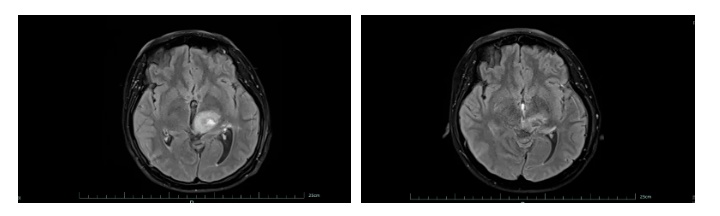

左为治疗前,右为治疗后。

好在经过系统治疗,王女士的肿瘤明显缩小,病情得到有效控制。目前,她已回归正常生活和工作,生活质量显著改善。